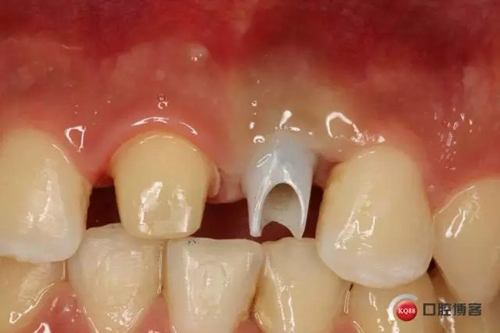

藻酸鹽對(duì)頜取模,超硬石膏灌注。發(fā)加工廠,與技工溝通注意事項(xiàng),等修復(fù)體做好后,檢查模型。是否就位,是否密合,預(yù)約患者復(fù)診戴牙,消毒修復(fù)區(qū),旋出愈合基臺(tái),定位器指導(dǎo)安放修復(fù)基臺(tái),試戴冠,調(diào)磨鄰接及 咬合至合適,拋光,患者滿意,加力扳手加力至30N,拍X片見就位良好,特芙蓉及暫封膏封中央螺絲孔,聚羧酸鋅粘固劑粘固,或是樹脂水門汀粘固,清理多余粘結(jié)劑,光固化樹脂封螺絲孔,拋光。術(shù)后注意隨訪。